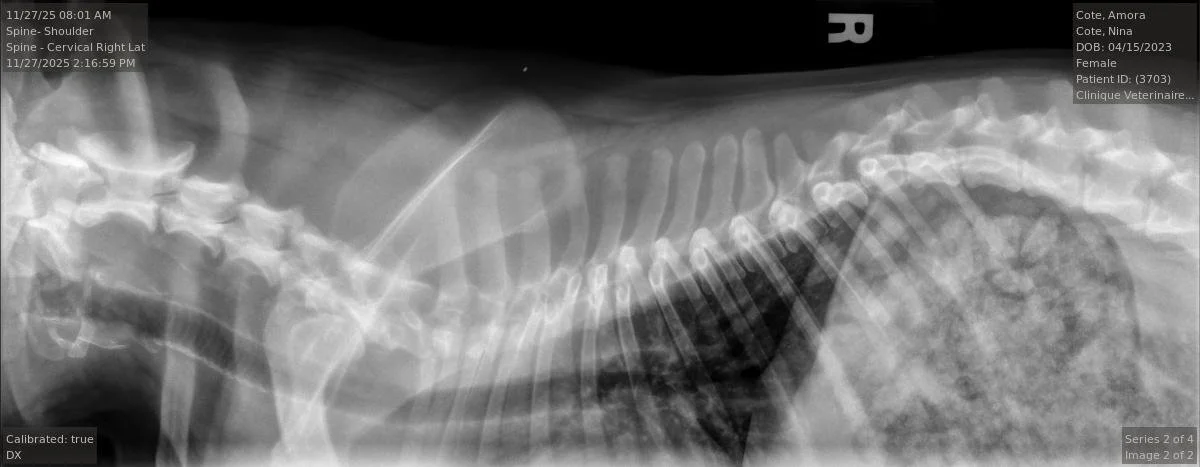

Testés OFA de la race pour Hanches, Coudes, Rotules, Trachée, Colonne Vertébrale, Yeux & Coeur.